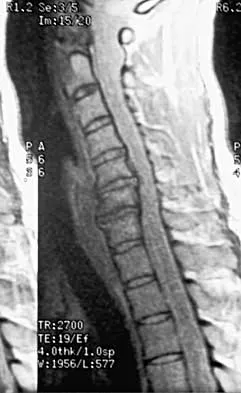

A 40-year-old carpenter has a 3-month history of right arm pain and neck pain that now leaves him unable to work. Examination reveals a positive Spurling test, weakness of the biceps, and a mildly positive Hoffman's sign on the right side. Electromyography and nerve conduction velocity studies show a right C6 deficit. Figures 27a through 27c show MRI scans that reveal two-level spondylotic disease at C5-6 and C6-7, a large herniated nucleus pulposus at C5-6, and a prominent ridge and hard disk at C6-7. Nonsurgical management fails to provide relief, so the patient elects surgical intervention. Which of the following surgical options would give the best long-term results?

Explanation

The patient has a single-level deficit by clinical examination but an adjacent level that may be pathologic. Hilibrand and associates, in a review of 374 patients with myeloradiculopathy treated with single-level or multilevel anterior cervical diskectomy and fusion, showed that 25% of patients had an occurrence of new radiculopathy or myelopathy at an adjacent level within 10 years after surgery. Reoperation rates were highest in those patients where the adjacent nonfused segment was C5-6 or C6-7. Those patients who had multilevel fusions had a lower incidence of adjacent segment disease. The authors recommended incorporating an adjacent level in the initial procedure in patients with myelopathy or radiculopathy when significant disease was noted. Posterior keyhole foraminotomy is an excellent procedure for single-level radiculopathy but is not effective in relieving myelopathy. Anterior cervical diskectomy without fusion has an increased incidence of hypermobility and neck pain on long-term follow-up. In a later review, these authors reported improved fusion rates and better clinical outcomes with the use of strut fusions instead of multilevel interbody grafts. Hilibrand AS, Carlson GD, Palumbo MA, Jones PK, Bohlman HH: Radiculopathy and myelopathy at segments adjacent to the site of a previous anterior cervical arthrodesis. J Bone Joint Surg Am 1999;81:519-528. Henderson CM, Hennessy RG, Shuey HM Jr, Shackelford EG: Posterior-lateral foraminotomy as an exclusive operative technique for cervical radiculopathy: A review of 846 consecutively operated cases. Neurosurgery 1983;13:504-512.